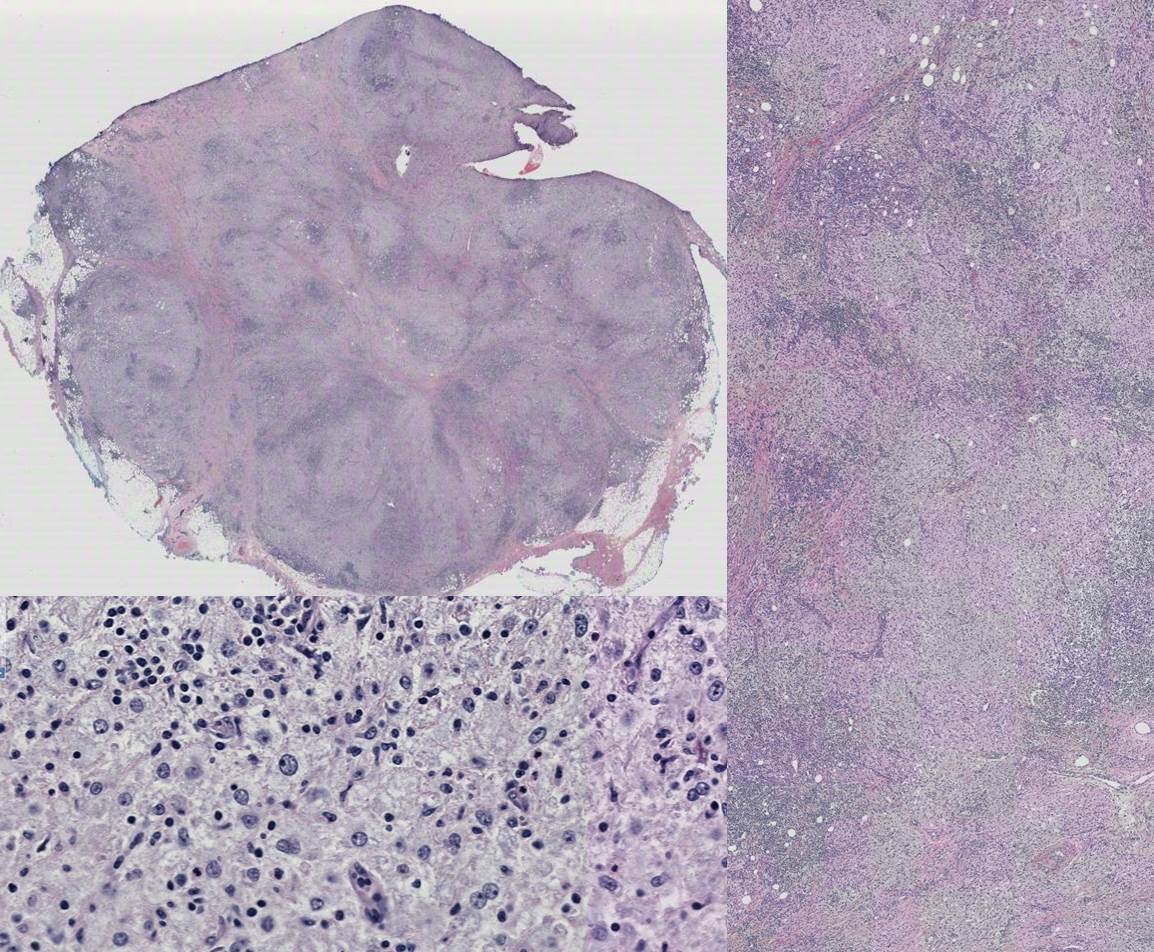

15 yo female with subcutaneous flank mass.

Rosai-Dorfman